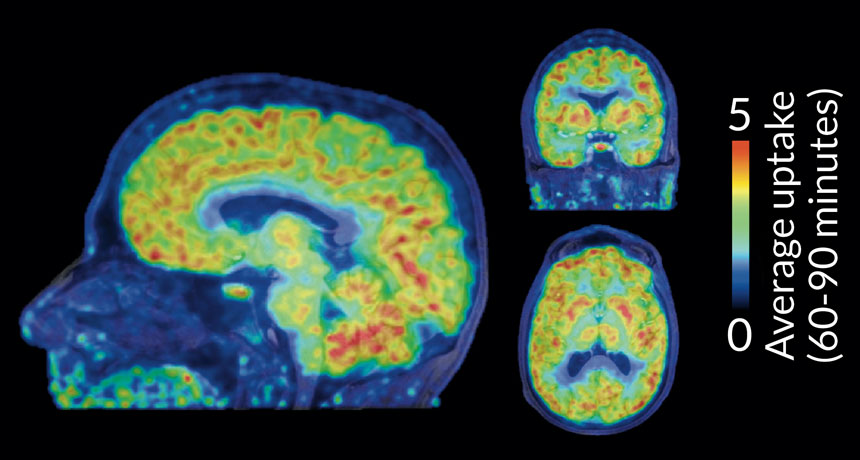

LEAVING A MARK A new radioactive tracer molecule shows where chemical tags, called epigenetic marks, are made in the brains of healthy people. Shown is the epigenetic activity in a volunteer’s brain imaged 60 to 90 minutes after injection of the tracer.

H.-Y. Wey et al./Science Translational Medicine 2016